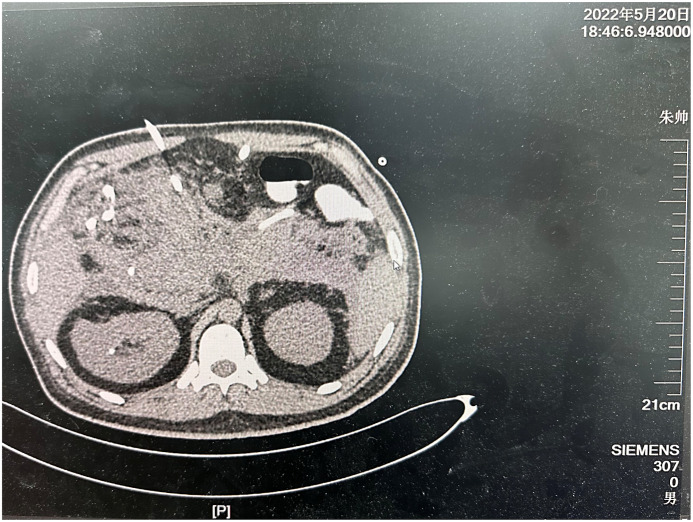

Case presentation: Here is the case history of a 31-year-old man already being treated for SAP. His condition was then complicated by massive, frequent intra-abdominal bleeding. The patient initially presented to the hospital with SAP. He was transferred to the intensive care unit for proper management. Massive intra-abdominal bleeds occurred on the 31st, 45th, and 60th days during hospitalization. The maximum blood loss was 1,500 mL. In each of the instances, digital subtraction angiography (DSA) embolization was carried out after the bleeding source had been verified. In order to manage SAP, continuous percutaneous drainage and staged pancreatic necrosectomy were undertaken for 6 months. No recurrence of intra-abdominal hemorrhage was detected. Infection of the abdominal cavity was properly controlled. The patient left the hospital in good condition.

Conclusion: Spontaneous bleeding in the abdominal cavity is a severe and life-threatening complication of SAP. This is often caused by vessel wall erosion. In such cases, DSA plays a crucial role in diagnosis and management. Besides precisely locating the bleeding source, one can perform a much-needed embolization immediately. Consequently, the disease is under total control, and the patient is much more likely to survive.